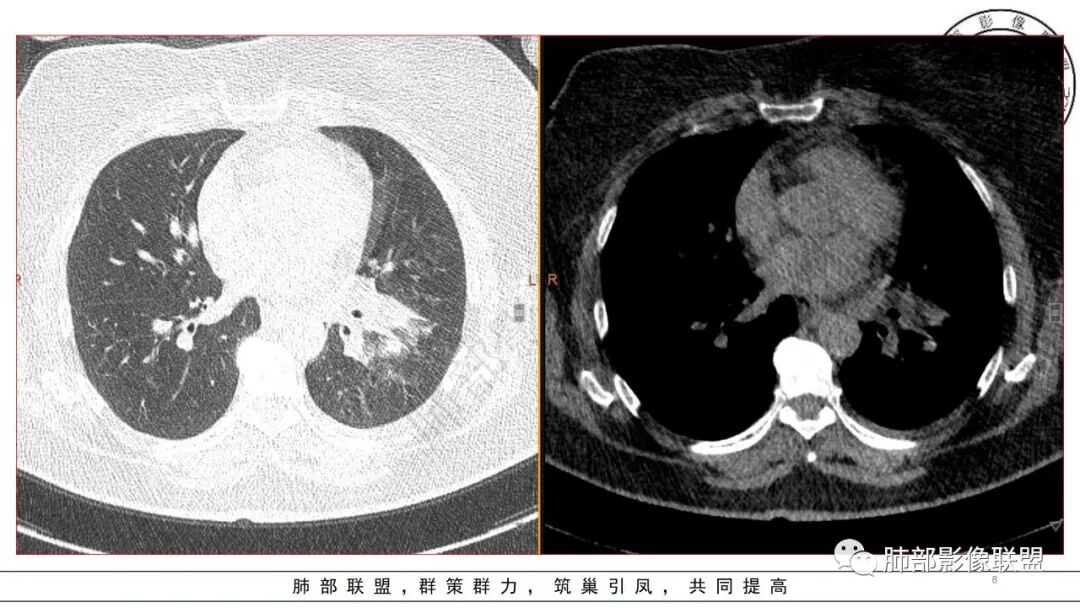

金葡菌气道来源很容易看到树芽征。

今天的晨读病例没看到树芽征,还是明显的肺泡病变

发一个金葡的对比一下

我这个也是金葡菌

3.金黄色葡萄球菌临床中毒症状明显,常寒颤高热起病,血源性感染者常有皮肤脓肿、伤口感染、蜂窝织炎、化脓性骨髓炎等等。病情变化快,影像进展迅速,短期内(如一两天内)迅速出现的有张力的菲薄气囊影,或多发成串分布的,尤具特征性!较之其他感染,短期内易出现脓胸。本例上述特征似乎不明显。

金葡应该也是血源性来源,因此也存在鉴别,区别在肝脏,肺克的血播是肝脏来源,金葡的血播可以各种来源,但是一般不会是肝脏来源,具体来说,金葡的SPE观察不那么典型,金葡可以形成更大的实变,肺克少一些,金葡的特征应该还是气囊,壁的张力更高,更薄,SPE似乎不明显,临床上皮肤软组织脓肿的有无,这个特征肺克应该不具有,但肺克一般有肝脓肿,没有的少见。